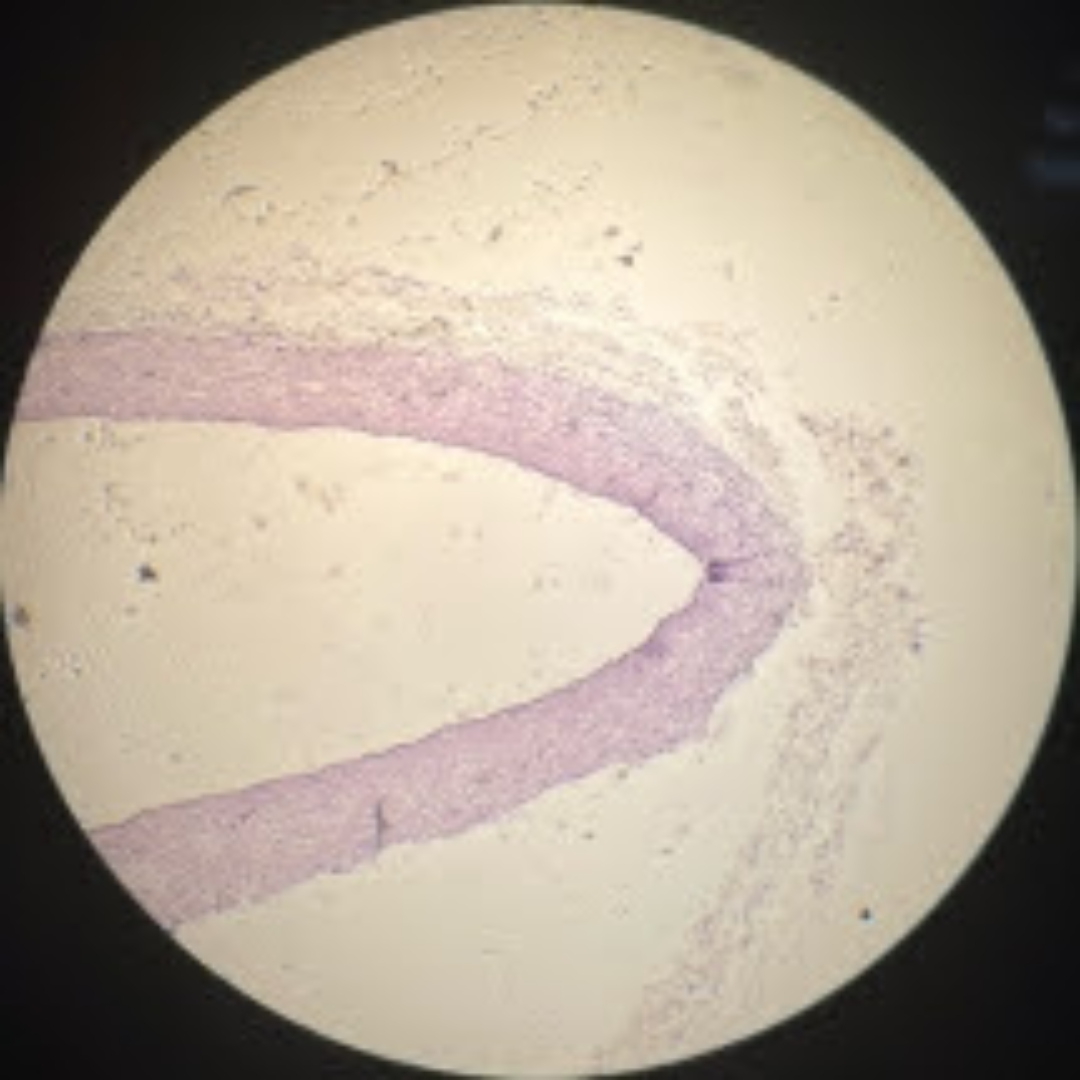

Hyaline Cartilage

Elastic Cartilage

Hyaline Cartilage